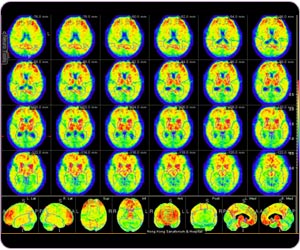

Region-based quantitative analysis for C-11 PIB brain study